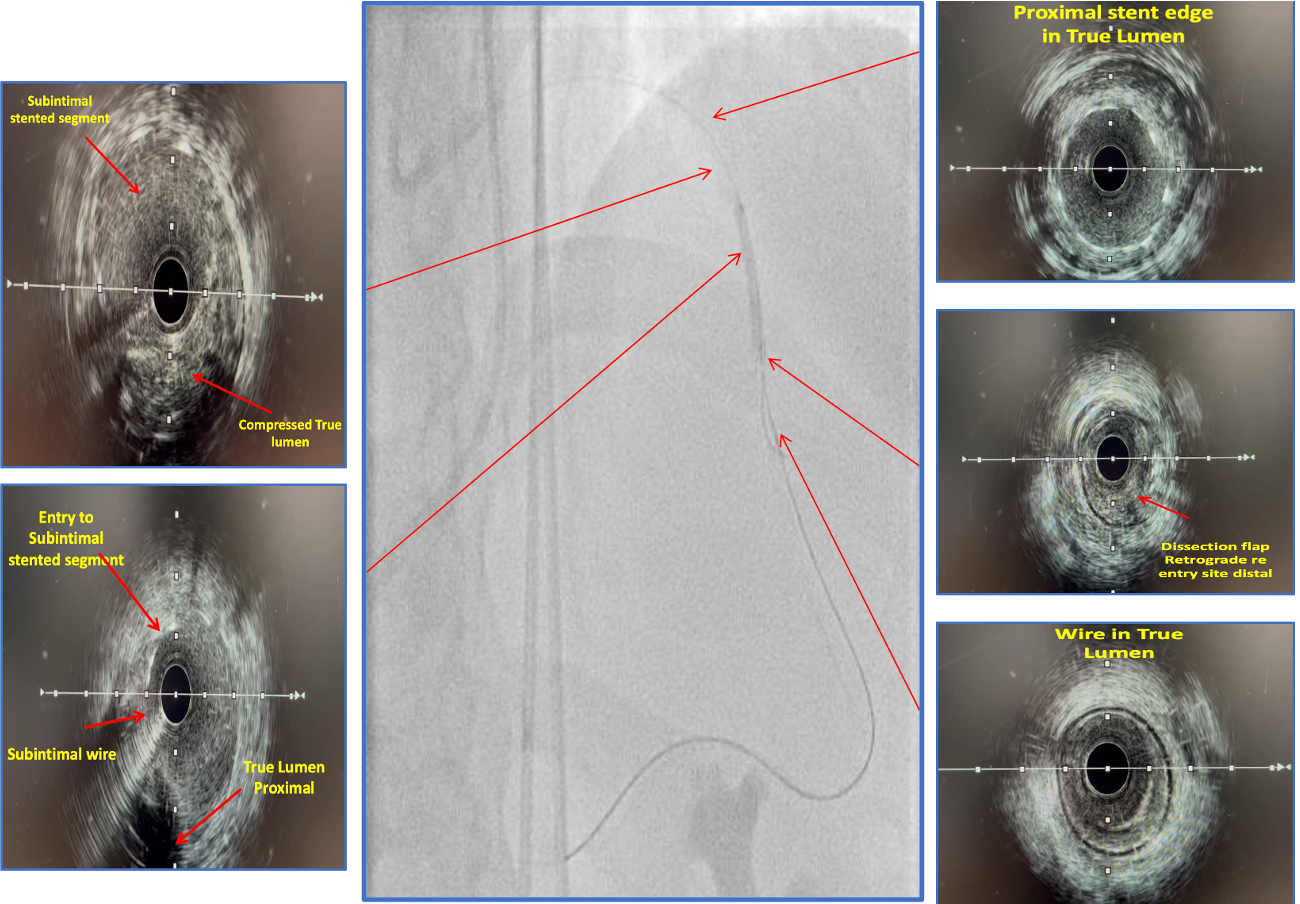

Diagnostic angiography demonstrated a borderline ostial LAD lesion followed by a proximal LAD CTO. The proximal edge of the previously deployed stent remained in the true lumen, while the majority of the stented segment tracked the subintimal plane with absent distal flow. The Left circumflex was without significant disease. The previously stented RCA was widely patent. Dual injections identified well-developed RCA-to-LAD collaterals

Bilateral femoral arterial access was obtained using 7F sheaths. The left main and RCA were engaged with 7F EBU 3.5 and JR 4 guide catheters, respectively. Antegrade CTO strategies were performed initially. Wire escalation with Gaia 3rd and Conquest Pro 12 supported by a Caravel microcatheter was attempted, followed by a parallel wire technique using a Sasuke dual-lumen microcatheter. Subsequently, antegrade fenestration and re-entry was attempted using a Corsair Pro and short balloon inflations. Despite multiple efforts, true lumen passage could not be re-established, and the antegrade strategy was abandoned. A retrograde approach was then employed. Attempts to cross septal collaterals from the RPDA and diagonal collaterals from the OM were unsuccessful. A contralateral epicardial collateral from the RCA marginal branch allowed successful retrograde advancement using a Suoh 3 wire with Caravel support. Reverse CART was executed by inflating a 3.0 ¡¿ 20 mm balloon within the subintimal stented plane, creating a controlled communication space. The retrograde Gaia 3rd wire entered this space and subsequently the antegrade true lumen, enabling RG3 externalization. Predilation was performed, and IVUS confirmed wire continuity from proximal true lumen to subintimal stented segment and distal true lumen. Three overlapping drug eluting stents (2.75 ¡¿ 28 mm, 3.0 ¡¿ 38 mm, 3.5 ¡¿ 38 mm) were deployed from mid LAD to ostial left main ending with a POT using NC Balloon 5.0 x 8mm.

Case Summary